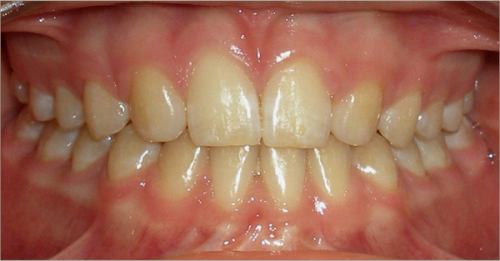

12 year old female:

Diagnosis:

- Missing upper right lateral incisor & lower right cuspid

- Horizontally impacted lower left cuspid

- Peg shaped upper left lateral incisor

Treatment:

- Extraction of impacted lower left cuspid, and peg shaped upper left lateral incisor

- Upper cuspids substituted as laterals

- Full fixed appliances

- 20 months